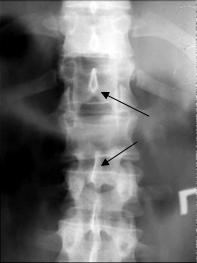

Признаками сгибательно-дистракционного повреждения является увеличение расстояния между соседними остистыми отростками на прямой и боковой рентгенограмме (рис. 3А) и локальный кифоз (рис. 3Б).

|

| А |

Б |

| Рис. 3. Рентгенологические признаки сгибательно-дистракционного повреждения |